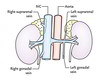

Optic nerve

32

What is E?

Pituitary stalk

33

What is F?

Internal carotid artery

34

What is G?

Cavernous sinus

35

What is H?